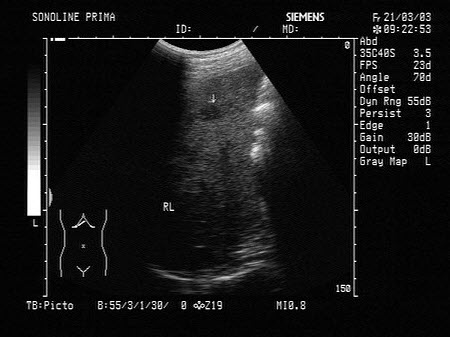

15、单项选择题

某患者,男,45岁,肝区不适,肝功能异常。行超声检查如图,诊断为()

A.弥漫性肝癌

B.结节状肝硬化

C.多发性血管瘤

D.血吸虫肝

E.不均匀性脂肪肝